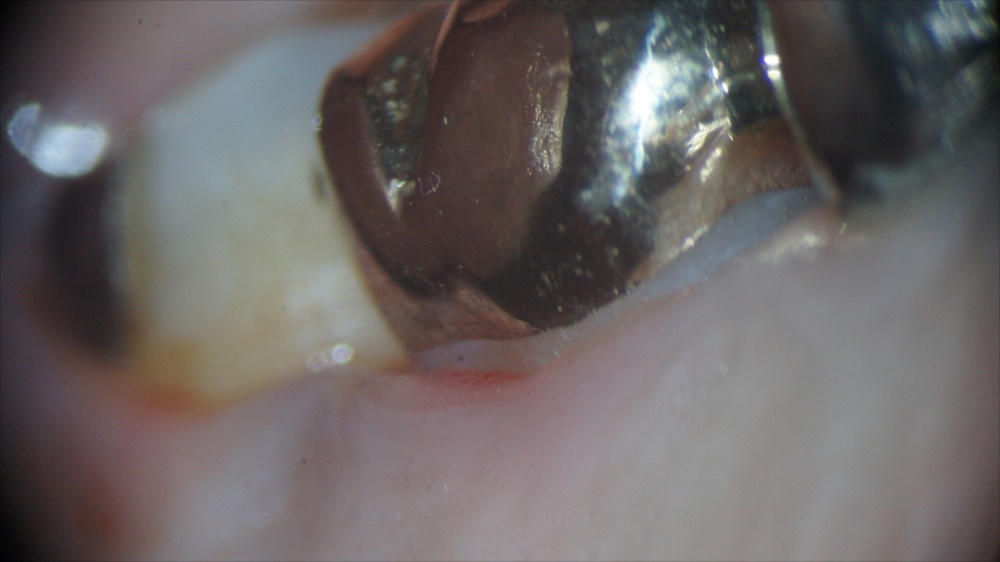

マイクロスコープで虫歯になっている歯を拡大してみているところ。

マイクロスコープで虫歯を確実に取り除いているところ。

虫歯を取りきったところの拡大写真。